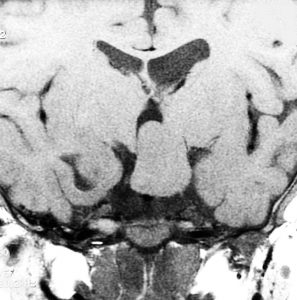

思春期早発で発症した幼児の視床下部過誤腫

視神経交叉の後方,乳頭体の前からぶら下がるようにしてあります

典型的な有茎状タイプです